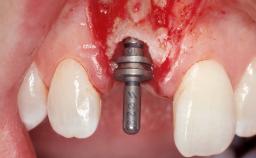

Late Flapless Placement of an Implant in a Maxillary Left Central Incisor Site

A 39-year-old male patient presented with a chief complaint of discomfort and gingival discoloration around his maxillary left central incisor. He was in good general health and was a non-smoker. His past dental history was significant because of the traumatic fracture of tooth 21 in a sporting accident at age 13. Initial dental treatment included endodontic therapy and a full-coverage restoration. The patient became symptomatic 5 years later, when structural failure of the tooth resulted in the dislodgment of the crown. Endodontic retreatment, apical surgery, and post-and-core restoration were performed.

Type of Implants One-Piece

Attachment One-Piece

Placement Protocol Early or late implant placement

Bone Volume Deficient horizontally, requiring prior grafting